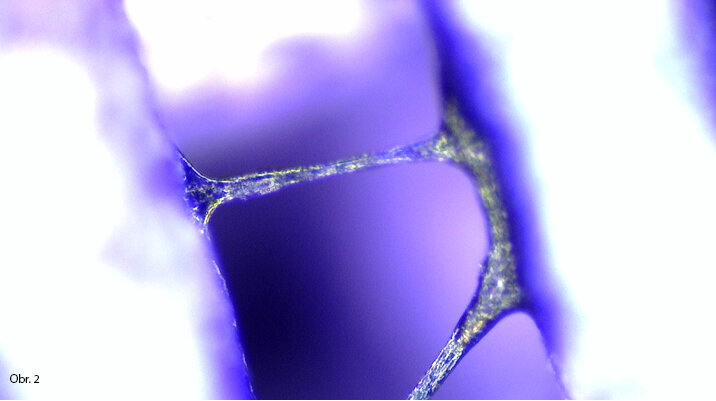

Konstrukce lešení vhodného pro speciální účely. Buňky jsou rozprostřeny na povrchu trámce scaffoldu. Reakce buněk je pozitivní.

Mezi trámci scaffoldu se vytváří buněčné můstky. Pokud je lešení degradovatelné, buňky vytváří náhradní tkáň.